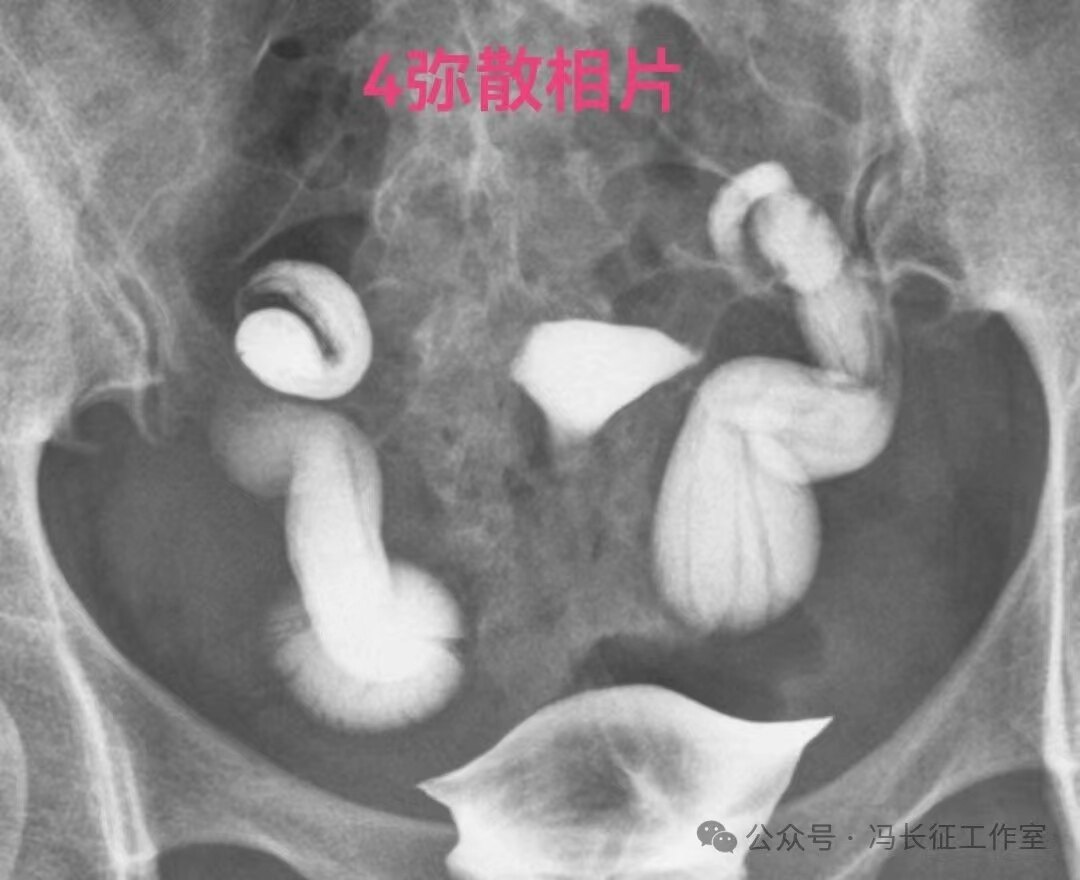

输卵管造影可以通过输卵管柔软度、近端是否和宫腔相通、积水输卵管粘膜情况、是否多囊、是否有造影剂进入盆腔弥散、管壁厚度六个方面对积水输卵管功能进行初步评估。提示输卵管功能好的征象:输卵管走行柔软、近端是否和宫腔相通、输卵管粘膜多,形态大致正常、单囊、弥散相有造影剂进入盆腔、管壁薄。提示输卵管功能受损或丧失的征象:输卵管走行僵硬、近端和宫腔不相通、管腔粘膜少或无、多囊、弥散相没有造影剂进入盆腔、管壁厚。

下面是一例输卵管功能良好的双侧输卵管积水的图片

双侧输卵管输卵管走行较自然柔软,近端和宫腔相通,输卵管粘膜丰富、单囊,双侧输卵管都向中间的子宫聚拢(提示输卵管系膜好),这些都提示双侧输卵管功能良好。虽然伞端没有造影剂进入盆腔弥散,输卵管管壁厚度和周围粘连情况未知;但是,从前面的信息可以初步估计输卵管功能良好。所以就给她做了腹腔镜行积水远端造口手,恢复伞部的拾卵功能,术后自然怀孕生育。